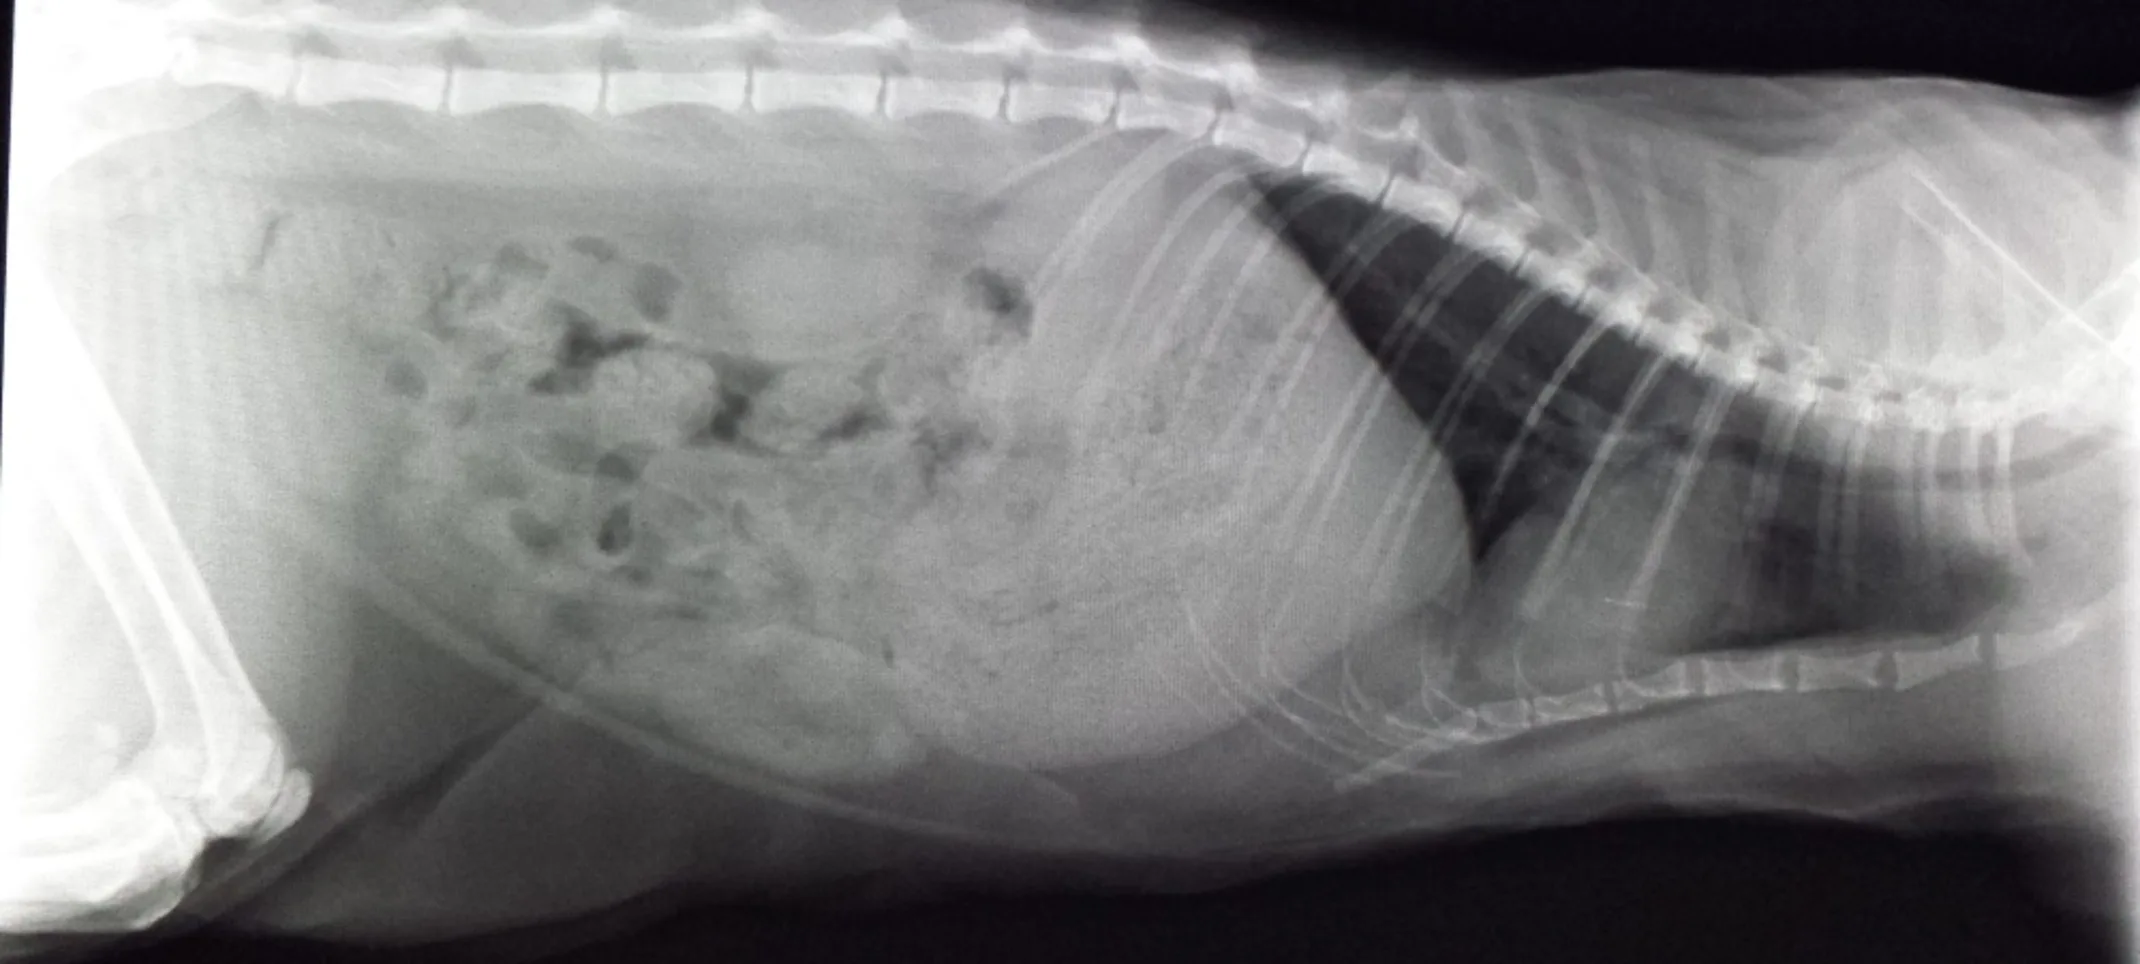

We’re equipped to perform routine radiography services to identify many types of illness or injury when pets are sick or suffer a trauma.

Radiology

Radiology is the primary diagnostic imaging tool in a veterinary practice. Our state of the art digital equipment includes access to specialists if needed.